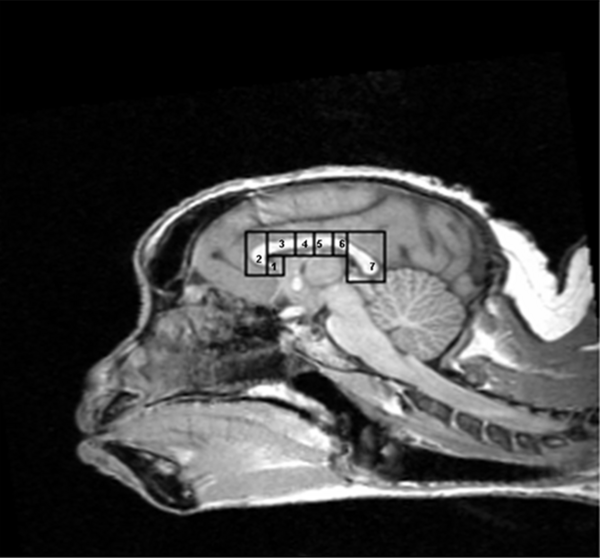

In the study, thirteen adult capuchins underwent magnetic resonance imaging of the brain to determine the size of their corpus callosum, which is the major white matter tract connecting the left and right cerebral hemispheres. The monkeys were later given a task to determine hand preference. The authors’ results led them to conclude that, as in humans, male capuchins have a smaller relative size of the corpus callosum than females, and right-handed individuals have a smaller relative size of the corpus callosum than left-handed individuals.

Article: Corpus Callosum Morphology in Capuchin Monkeys Is Influenced by Sex and Handedness